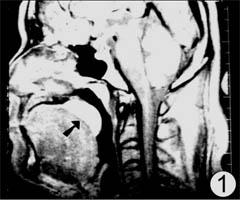

圖 軟齶肥厚,口咽部正中矢狀面T1加權圖像,示軟齶厚度顯 著大於正常人軟齶之最大值 口咽軟齶後橫斷面,T1加權圖像用ROI技術測量口咽腔截面積,該正常人為174mm2

口咽腔的狹窄往往是口咽諸多軟組織改變的綜合結果,單單某一結構的增生、肥厚往往部不足以造成口咽腔的狹窄,例如本研究50例正常人中有9例軟齶較厚、較長,6例側咽壁增厚,4例舌根有後移,但均無打鼾或睡眠中憋醒的症狀。因此,口咽腔截面積的觀察顯得十分重要,它反映了口咽腔前、後及兩側壁軟組織改變的綜合結果。本組29例OSAS患者軟齶後口咽腔截面積為51.4±20.3mm2,顯著地小於對照組截面積156.1±62.7mm2(P<0.01),因此,我們認為,軟齶後截面積小於70mm2,是判斷口咽腔狹窄的參考標準。舌後區截面積患者組和對照組無統計學差異(P>0.05)。軟齶在一般狀態下貼附於舌表面,睡眠時可下垂於口咽腔,軟齶的厚肥、變長增加了呼吸時空氣阻力,減少了口咽腔有效容積。側咽壁構成口咽的主要部分,它的增厚是口咽腔變窄的主要原因,本組29例OSAS側咽壁厚度均大於正常人側咽壁的最大厚度。